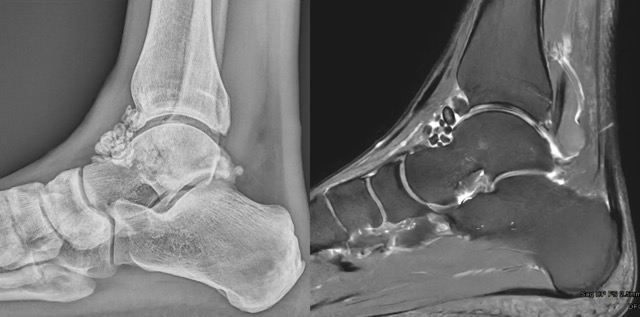

ARTHRO-SCANNER ET ARTHRO-IRM

Nodules moulés

Lésions (cartilages, tendons, ligaments…)